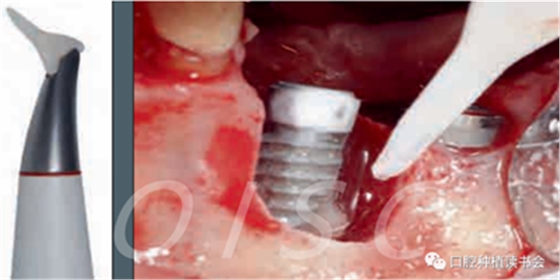

單純使用激光或噴砂對種植體周圍炎進(jìn)行非手術(shù)治療效果不佳;研究表明化學(xué)療法和機(jī)械清創(chuàng)作用也不大;使用光動力療法治療種植體周圍炎的嘗試也沒有取得成功(圖3)。因此,我們可以確認(rèn):非手術(shù)治療的方法并不能阻止種植體周圍炎病情的發(fā)展

圖3 手術(shù)中使用噴砂裝置清潔暴露的種植體表面